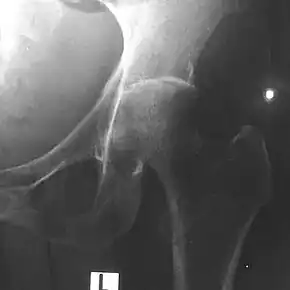

Depending on the course of infection, other severe manifestations develop. About 1 to 5% of those infected develop inflammation of the brain and brain covering or collection of pus in the brain; 14 to 28% develop bacterial inflammation of the kidneys, kidney abscess or prostatic abscesses; 0 to 30% develop neck or salivary gland abscesses; 10 to 33% develop liver, spleen, or paraintestinal abscesses; 4 to 14% develop septic arthritis and osteomyelitis.[1] Rare manifestations include lymph node disease resembling tuberculosis,[9] mediastinal masses, collection of fluid in the heart covering,[3] abnormal dilatation of blood vessels due to infection,[1] and inflammation of the pancreas.[3] In Australia, up to 20% of infected males develop prostatic abscess characterized by pain during urination, difficulty in passing urine, and urinary retention requiring catheterisation.[1] Rectal examination shows inflammation of the prostate.[3] In Thailand, 30% of the infected children develop parotid abscesses.[1] Encephalomyelitis can occur in healthy people without risk factors. Those with melioidosis encephomyelitis tend to have normal computed tomography scans, but increased T2 signal by magnetic resonance imaging, extending to the brain stem and spinal cord. Clinical signs include: unilateral upper motor neuron limb weakness, cerebellar signs, and cranial nerve palsies (VI, VII nerve palsies and bulbar palsy). Some cases presented with flaccid paralysis alone.[3] In northern Australia, all melioidosis with encephalomyelitis cases had elevated white cells in the cerebrospinal fluid (CSF), mostly mononuclear cells with elevated CSF protein.[9]

Surgery